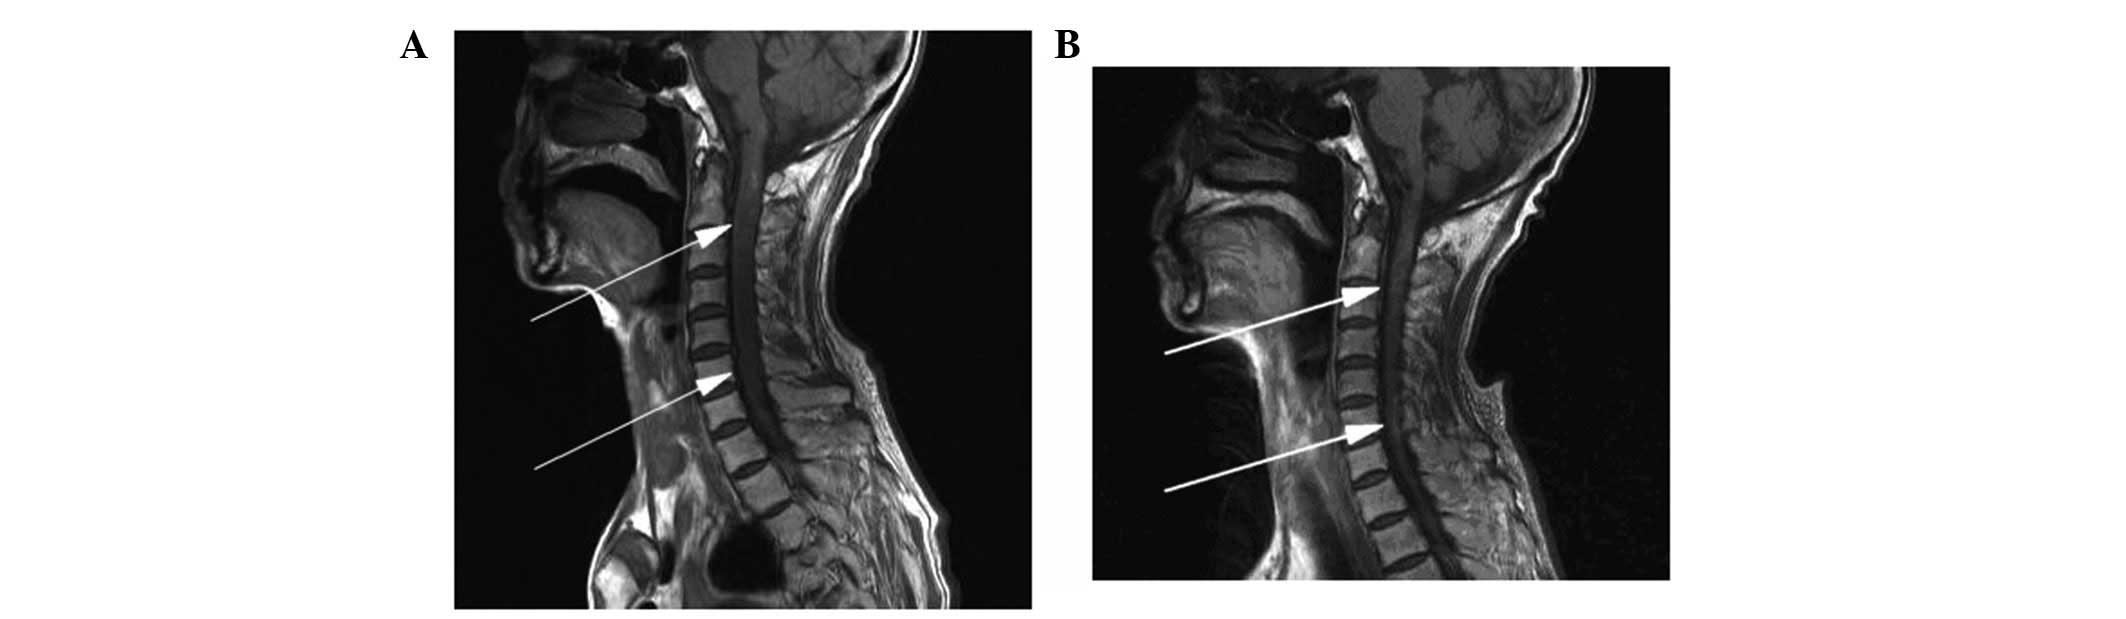

Comparison between the MR images of the cervical spinal cord prior to and following treatment. Sagittal T1-weighted images performed (A) prior to chemotherapy (MR 10-28-2009) showing abnormal signals in the medulla oblongata and cervical cord, considered to be the metastatic lesions (indicated by the two arrows), and (B) following chemotherapy (MR-11-23-2009) showing that the abnormal signals of the medulla oblongata and cervical cord had markedly improved (indicated by the two arrows). MR, magnetic resonance.

The patient complained of constant occipital headache with slight pain in the bilateral upper arm and fatigue, but no nausea or vomiting, for 2.7 months after the treatment of the primary lesion. The Karnofsky performance status (KPS) score was 70 and no pathological reflexes were observed on physical examination. Brain MRI revealed two nodules (0.35 and 0.8 cm in diameter) in the right cerebellar hemisphere. The signal was slightly lower in the unenhanced T1-weighted images and slightly higher in the T2-weighted images. The lesions showed clear ring-like, uniform hardening on signal-enhanced scans, and mild edema was observed surrounding the larger lesion. The diagnosis was of a cerebellar metastasis from the esophageal cancer following treatment (Figs. 3–5). Following whole brain radiotherapy of a total dose of 30 Gy/20 fractions of 1.5 Gy per fraction by hyperfractionation (two fractions per day), the patient’s occipital headache was relieved, however, the neck numbness was aggravated. A cervical MRI examination revealed enlargement of the medulla oblongata and spinal cord, with slightly increased T1 and T2 signals. A signal-enhanced scan showed heterogeneous enhancement in a region considered to be the metastasis. The patient continued with the planned whole brain radiotherapy, together with nedaplatin chemotherapy (40 mg on days one to three of the radiotherapy period). At the end of the first period of chemotherapy, the patient’s occipital headaches were alleviated and the neck numbness was markedly improved. One month later, the patient’s head and neck symptoms had further improved and a neck MRI revealed that the abnormal signal foci in the medulla oblongata and cervical cord had also markedly improved (Figs. 6 and 7). To strengthen the effects of the treatment, the patient was treated with palliative radiotherapy (total dose of 26 Gy/13 fractions of 2 Gy per fraction) to the cervical spinal cord. Following treatment, the patient’s head and neck pain and numbness symptoms had almost disappeared. The patient was discharged with oral etoposide (VP-16) capsules (50 mg daily for 20 days).

Figure 6

Comparison between the MR images of the cervical spinal cord prior to and following chemotherapy. Sagittal T2WI (A) prior to chemotherapy (MR 10-28-2009) showing increased T2WI signals and abnormal morphological augmentation in the medulla oblongata and cervical cord indicating metastatic lesions (indicated by the two arrows), and (B) following chemotherapy (MR 11-23-2009) showing decreased T2WI signals in the medulla oblongata and cervical cord consistent with the signals of normal tissues, and marked improvement in the abnormal morphology (as indicated by the two arrows). MR, magnetic resonance; T2WI, T2-weighted image.